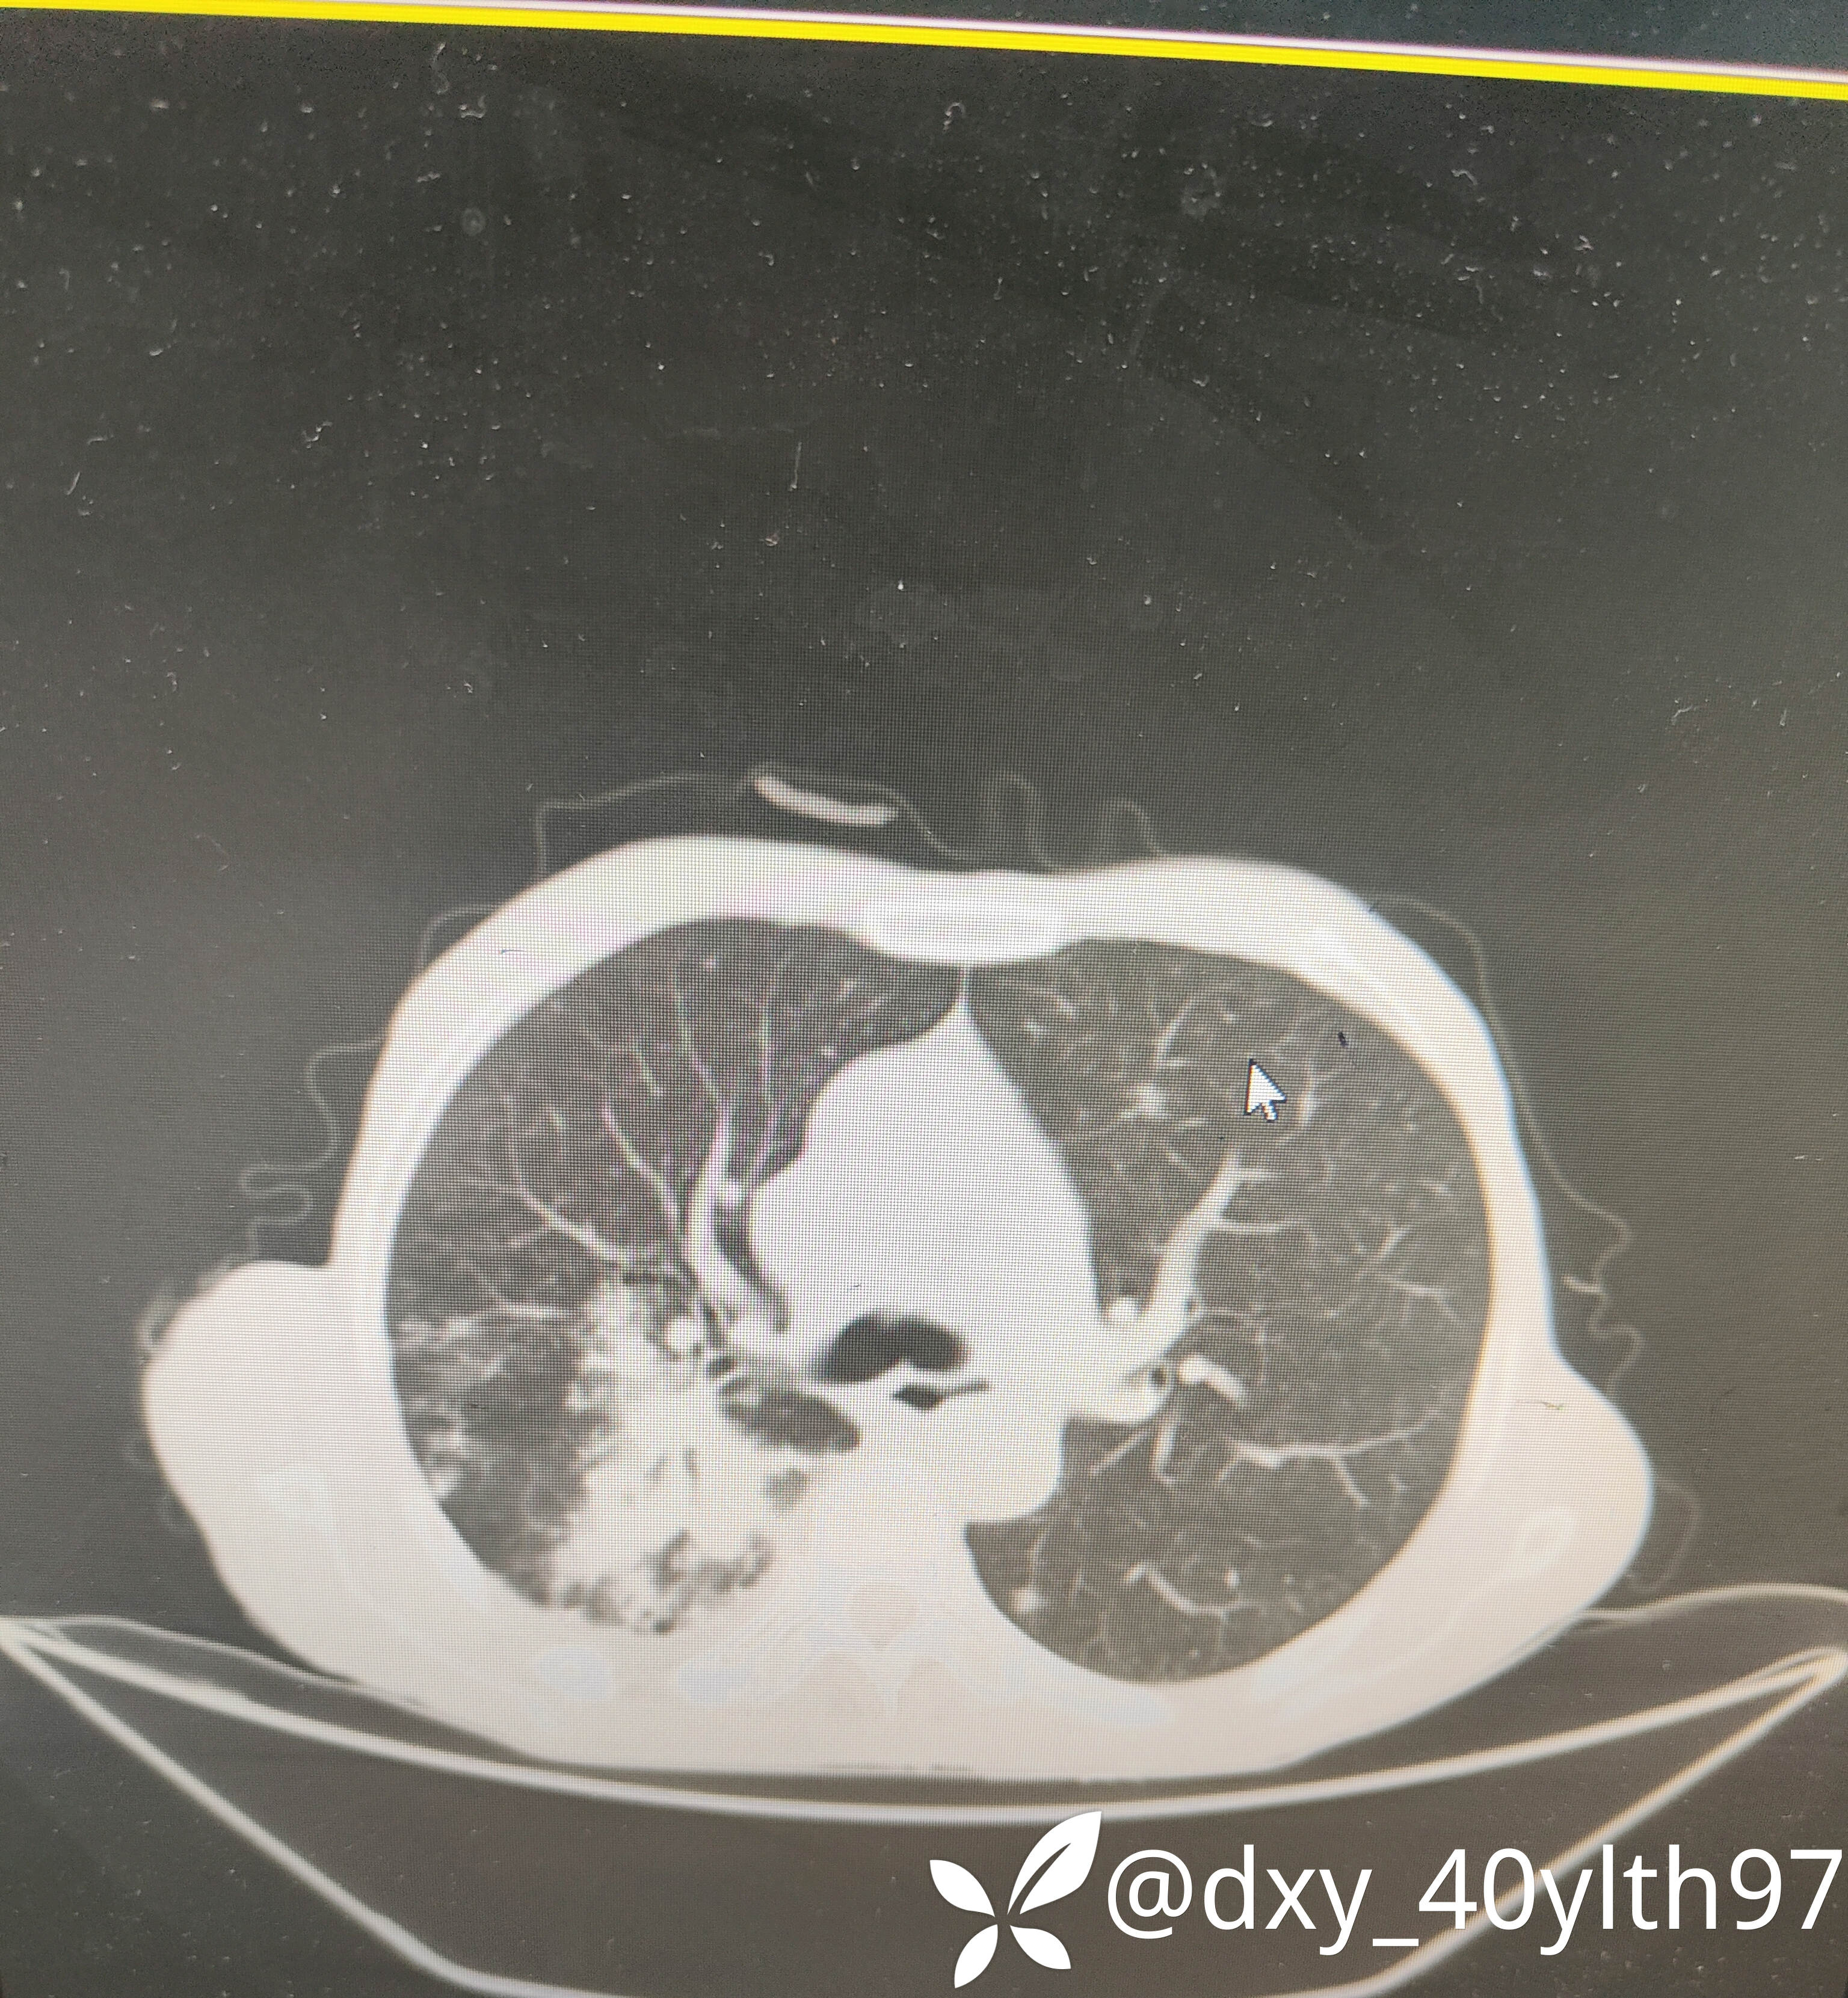

2023年8月肺部CT平扫影像结果提示:1.右肺上叶密度增高影较前显著增大,建议进一步检查;2.两肺多发斑片结节灶较前增多,部分增大。

肺部增强CT影像学提示:右肺内大片不规则影轻度强化,肿瘤可能。